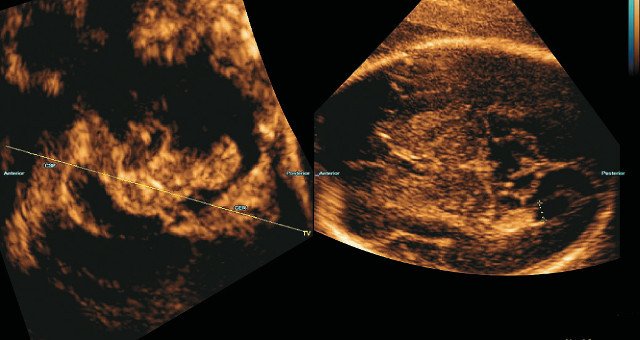

Объемные изображения головного мозга обычно получают, начиная с поперечного изображения головки плода на уровне трансмозжечковой аксиальной плоскости, направляя исходящий ультразвуковой сигнал под углом приблизительно 45° к срединной линии головного мозга, чтобы минимизировать акустическую тень от основания черепа на структуры мозга в реконструированных плоскостях (рис. 1). Угол развертки в зависимости от срока беременности устанавливают в пределах 40-60°, чтобы головной мозг плода целиком попал в объемное изображение.

Из изображения в этой проекции получают объемное изображение ЦНС. Срединная линия выбрана косой, чтобы минимизировать акустическую тень черепа. На изображение наложена рамка области интереса (ROI; зеленая линия).